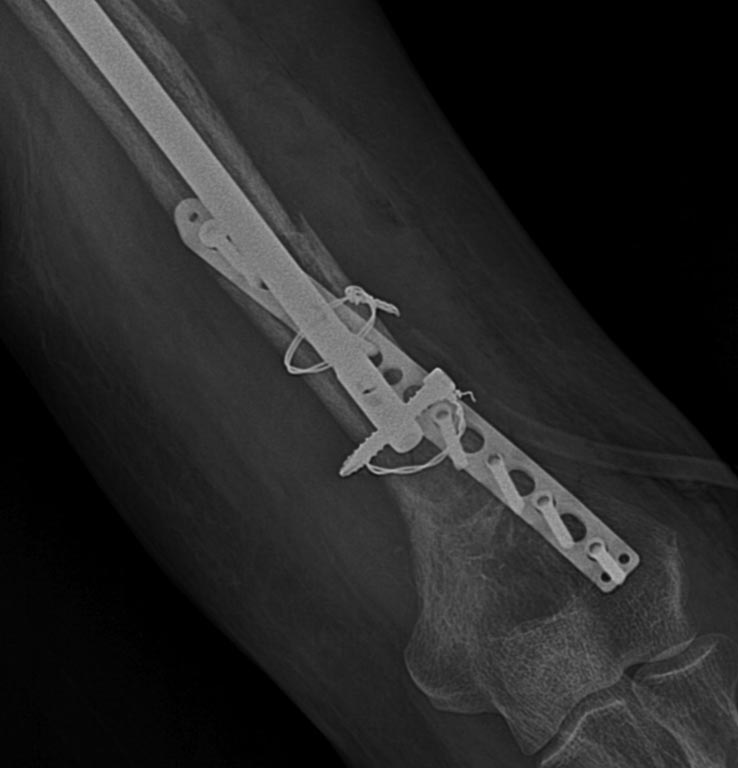

Стас 07 Ноябрь 2017, 13:40

Rg

всем добрый день)сегодня прооперировали пациента.из заднего доступа открылись,дистальный блокирующий финт удалили легко,зажимом пропихнули к передней поверхности,2 цыркляжа,пластина и удалось выполнить блокирование гвоздя с межфрагментарной компрессией правда в одном отверстии ,проксимальнее не получилось так как винт болтался и его не стали ставить.фиксация достаточно стабильная .гипс наложим.снимки скину позже,всем спасибо за обсуждение)))